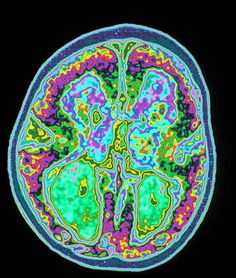

Перфузионно-взвешенные МРТ во многом аналогичны перфузионным изображениям при КТ. Т2-градиентные МРТ отражают магнитную чувствительность. Яркий сигнал на ДВИ МРТ коррелирует со снижением кровотока на перфузионно-взвешенных МРТ головного мозга.

МРТ головного мозга. Перфузионно-взвешенная МРТ. Снижение кровотока в левой лобной доле.

МРТ головного мозга. Сопоставление диффузионно-взвешенной и перфузионно-взвешенной МРТ.